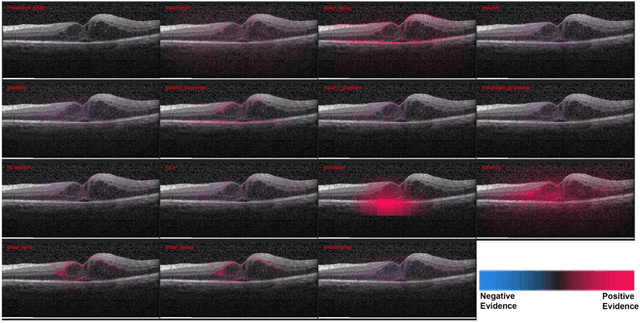

Abstract:Background: The lack of explanations for the decisions made by algorithms such as deep learning has hampered their acceptance by the clinical community despite highly accurate results on multiple problems. Recently, attribution methods have emerged for explaining deep learning models, and they have been tested on medical imaging problems. The performance of attribution methods is compared on standard machine learning datasets and not on medical images. In this study, we perform a comparative analysis to determine the most suitable explainability method for retinal OCT diagnosis. Methods: A commonly used deep learning model known as Inception v3 was trained to diagnose 3 retinal diseases - choroidal neovascularization (CNV), diabetic macular edema (DME), and drusen. The explanations from 13 different attribution methods were rated by a panel of 14 clinicians for clinical significance. Feedback was obtained from the clinicians regarding the current and future scope of such methods. Results: An attribution method based on a Taylor series expansion, called Deep Taylor was rated the highest by clinicians with a median rating of 3.85/5. It was followed by two other attribution methods, Guided backpropagation and SHAP (SHapley Additive exPlanations). Conclusion: Explanations of deep learning models can make them more transparent for clinical diagnosis. This study compared different explanations methods in the context of retinal OCT diagnosis and found that the best performing method may not be the one considered best for other deep learning tasks. Overall, there was a high degree of acceptance from the clinicians surveyed in the study. Keywords: explainable AI, deep learning, machine learning, image processing, Optical coherence tomography, retina, Diabetic macular edema, Choroidal Neovascularization, Drusen